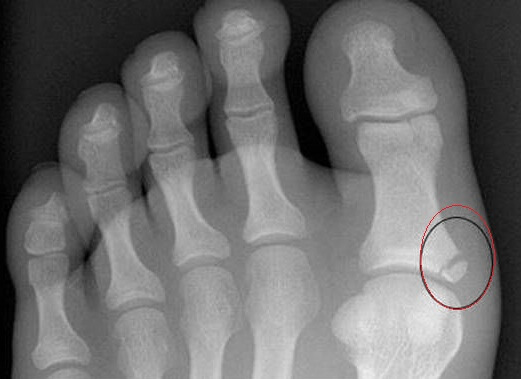

осколок при переломе пальца ноги

Линия разлома может находиться на любом участке фаланги пальца. Иногда повреждение случается одновременно на нескольких фалангах.

При наличии подобных признаков можно со 100%-й уверенностью говорить о переломе. Все манипуляции, связанные с прощупыванием кости, выполняются с максимальной осторожностью и только силами специалиста. Закрытый перелом требует проведения рентгенографии. Это один из основных методов, как определить перелом с высокой точностью.